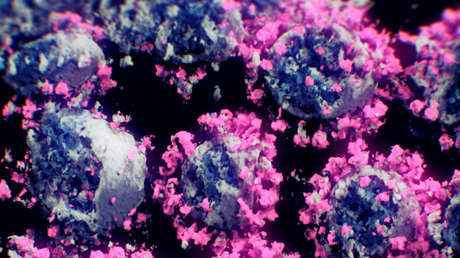

La familia de los virus ARN con envoltura, la llamada coronaviridae, incluye a siete virus, entre ellos el SARS-CoV-2, causante del covid-19. Cuatro de ellos —HCoV-229E, HCoV-NL63, HCoV-HKU1, y HCoV-OC43— normalmente están asociados con infecciones respiratorias no letales. En cuanto al MERS-CoV y el SARS-CoV, pueden provocar daños graves en la salud, siendo potencialmente mortales.

Los investigadores usaron una nueva tecnología denominada PepSeq para estudiar la respuesta de los anticuerpos a todos los coronavirus que infectan a los humanos, comparando los patrones de reactividad. En consecuencia, demostraron que el SARS-CoV-2 puede provocar la reacción de los anticuerpos del sistema inmunológico creados inicialmente en respuesta a las anteriores infecciones.